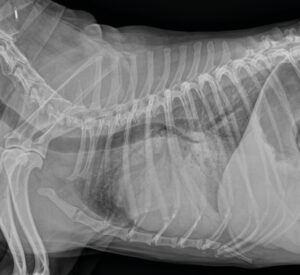

Perro mestizo, macho de 12 años de edad. Ha sufrido un desmayo. Hay ascitis y se ausculta soplo. Cardiomegalia. Se encuentra en tratamiento con pimobendan 5 mg BID.